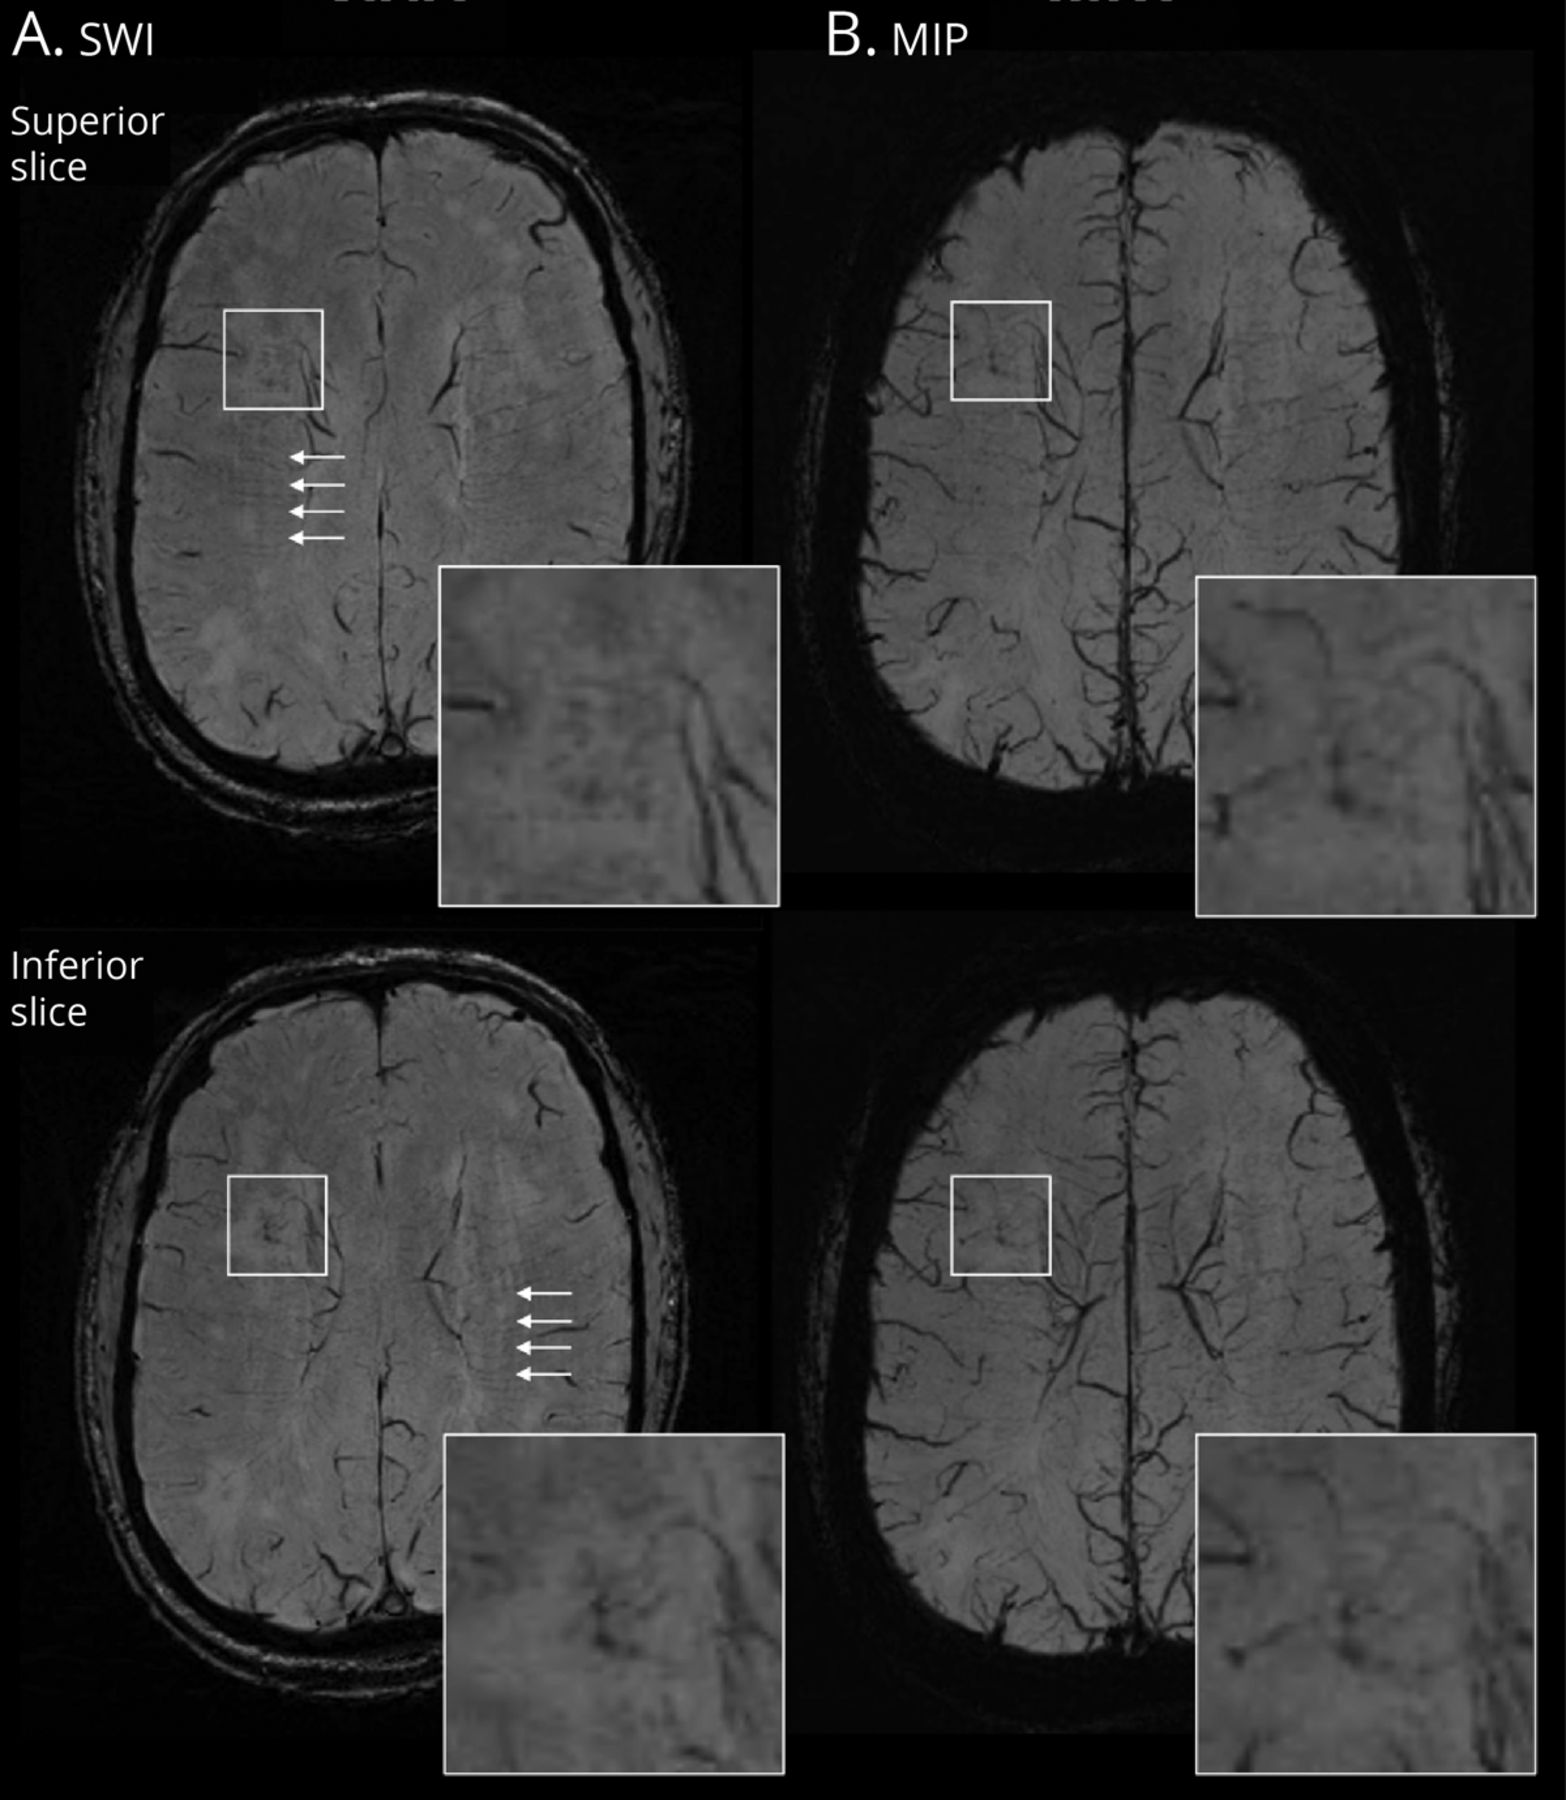

总共有94 vessel-clusters 36例中被识别。48 94 vessel-clusters(51%)位于左半球,94年22(23%)位于前55(58.5%)在中间,和17(18%),后深白质。中值(差)的体积区域包含vessel-cluster 0.15毫升(0.08 - -0.26),而45 (48%)vessel-clusters圆形,卵形的32例(34%),不规则的6例(6%),11(12%)和线性。在94 vessel-clusters,其中27显示集群或链接低信号点或线,似乎对应1主要vessel-like结构(29%),而集群的多个vessel-like结构(5)观察67年(71%),其余的中位数2 (1 - 3)vessel-like结构/ vessel-cluster(例子图1和eFigure 5,links.lww.com/WNL/C29)。vessel-like结构的可追溯性的一个例子在瑞士和MIP通过连续轴向飞机所示图4。十二vessel-clusters(13%)与noncavitated负责人,45(48%)部分空泡研究负责人,完成蛀牙和37例(40%)。Vessel-clusters多种血管覆盖更大的体积比single-vessel-like结构(中位数(差)卷(mL): 0.17(0.98 - -0.30)和0.09(0.5 - -0.20),分别p= 0.005),更有可能是与完全形成空洞病变(n [%], [49] 33 vs 4 [15],p= 0.002),更有可能显示为一个线性边缘(n [%], [44] 37 vs 4 [15],p< 0.001),但没有白色物质的不同位置(p= 0.186)。12 vessel-clusters noncavitated对应区域,我们观察到1的主要扩张血管内一个区域负责人(eFigure 5,links.lww.com/WNL/C29),而vessel-clusters相关部分和完全空化(分别为33%和70%)有一个线性低信号边缘出现在瑞士的边缘腔(图1)。可用的更多细节结构vessel-cluster特性eTable 3。

代表vessel-cluster连续出现在轴向片零星的小血管疾病患者。vessel-cluster(广场)2所示连续轴向片(优越伪劣)susceptibility-weighted成像(瑞士,)和最大强度投影(MIP, B)序列。增强的vessel-cluster地区,小血管清晰可见点的外观可追踪的连续切片或MIP序列增强这些结构通过不同飞机的可见性。注意到大部分的船只从集群收敛于静脉深静脉系统,但这些血管的分布是无序的,不同于正常平行的外观深髓小静脉中可见椎体semiovale(白色箭头)。